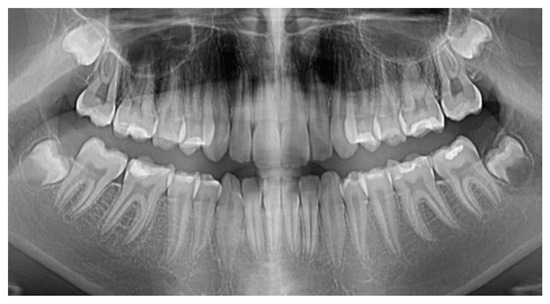

The Combination of Diode Laser and Ozonated Water in the Treatment of Complicated Pulp Gangrene

2. Materials and Methods

2.1. Study Participant